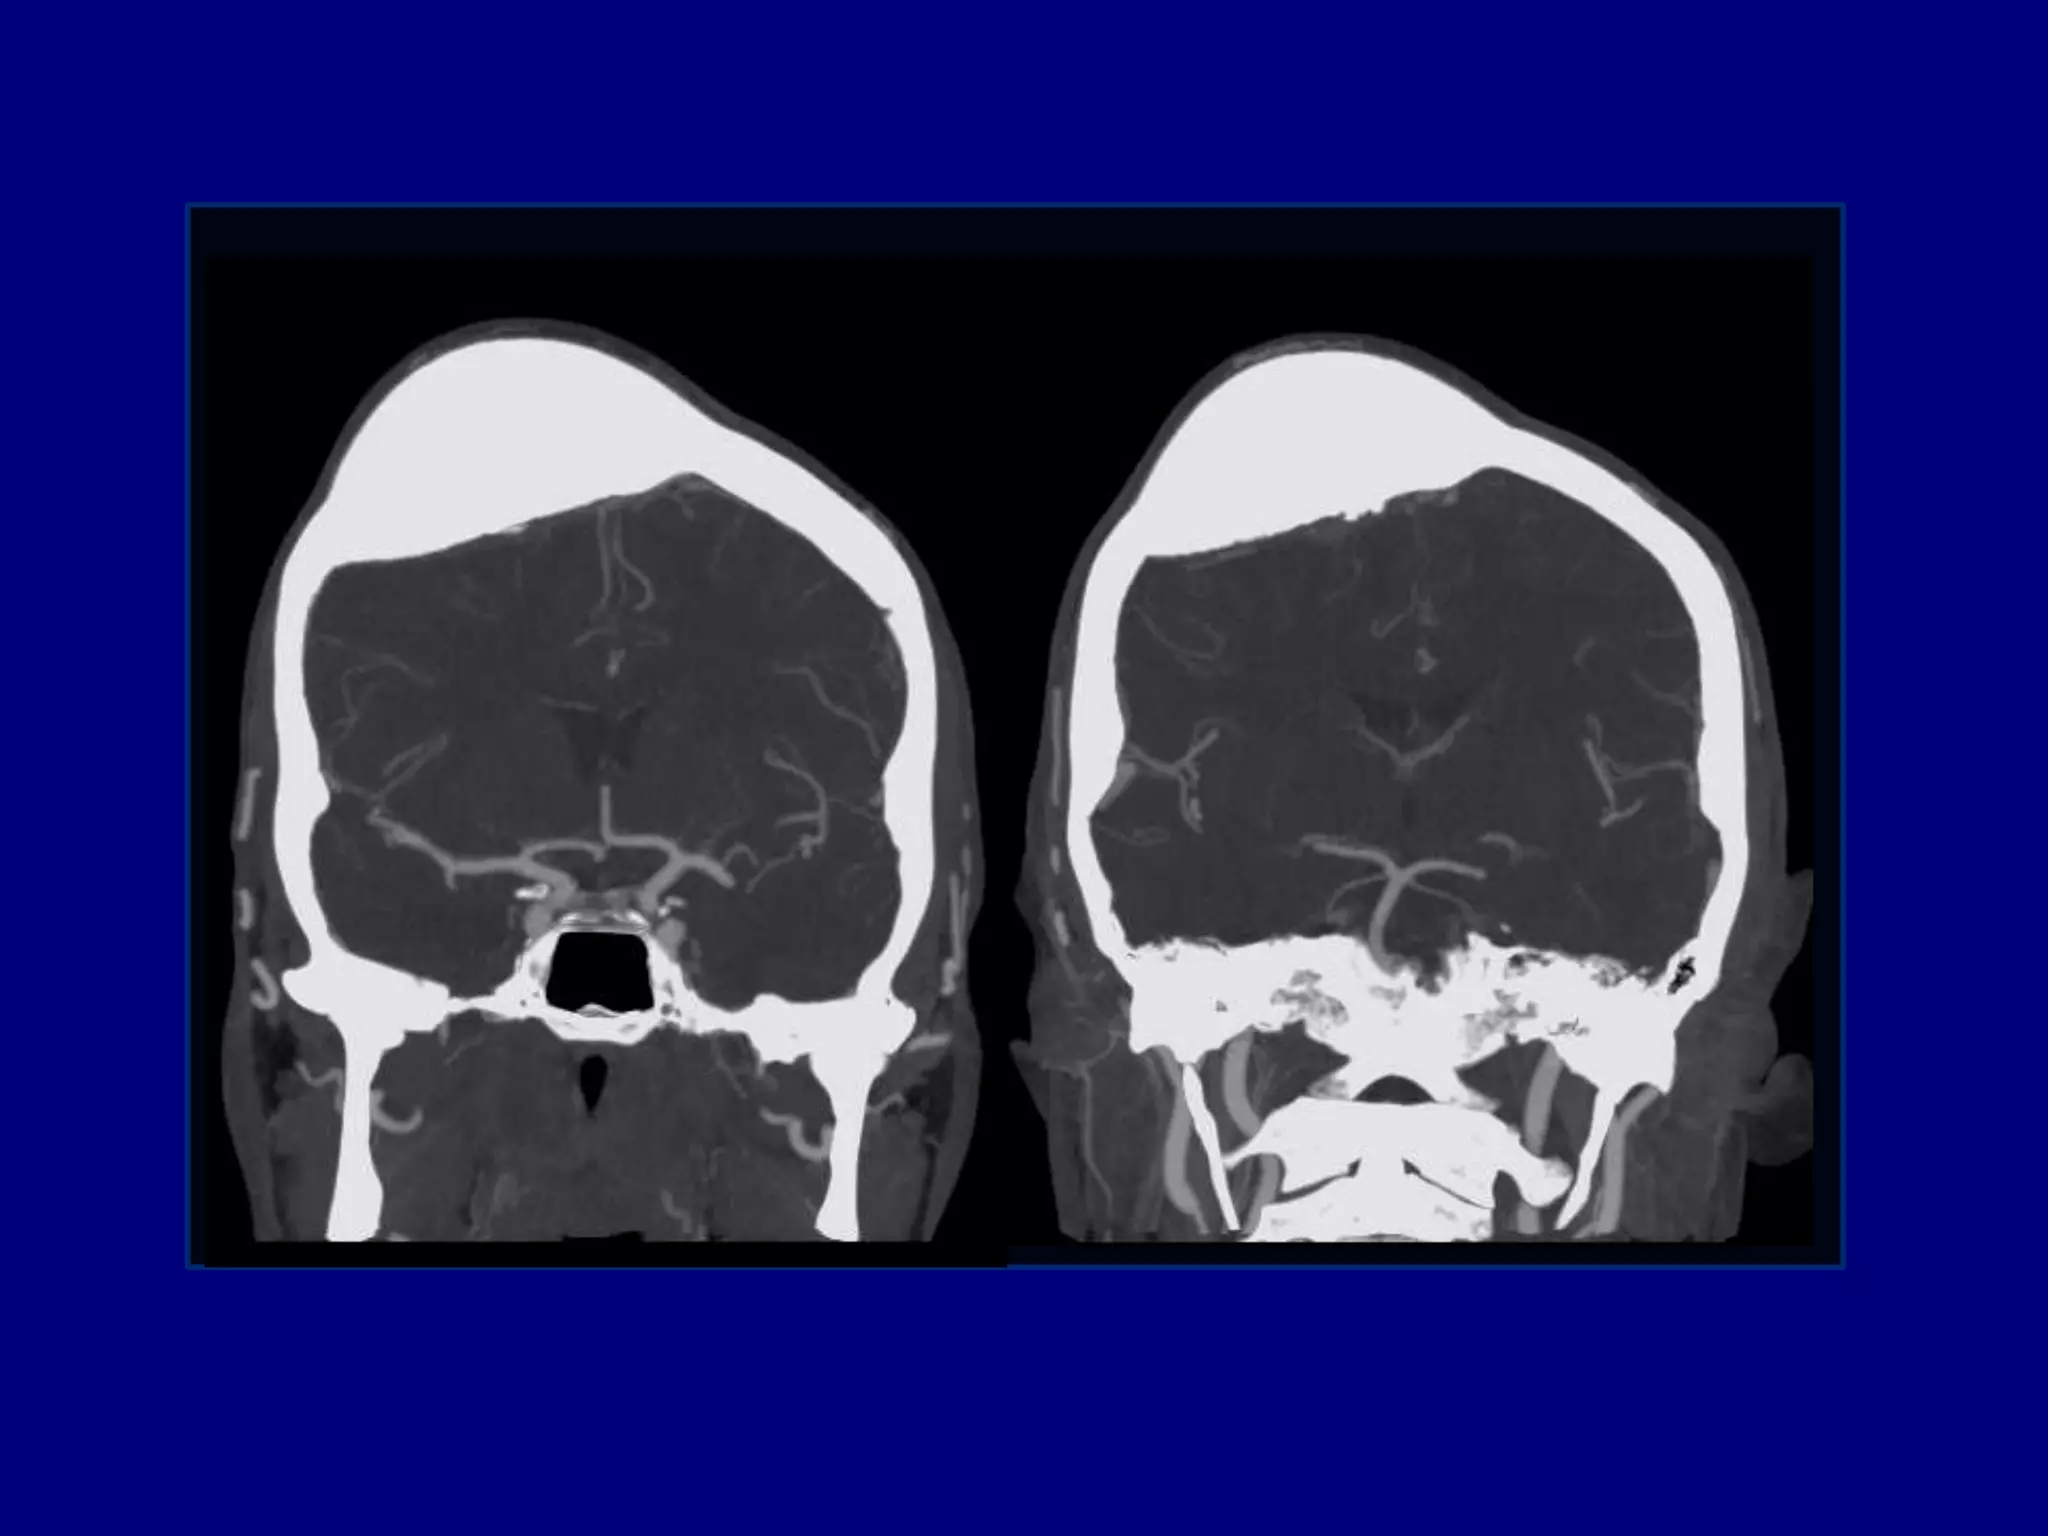

Subcortical hyperdense masses in the left fronto-parietal lobes

with surrounding hypodensities extending to basal ganglia

CT

 Hyperdense lesions ( 70%). Hemorrhage is uncommon